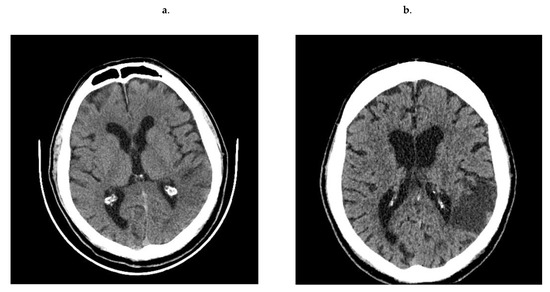

Patients positively recruited presented clinical symptoms of stroke lasting no longer than 24 h, confirmed by neurological examination and/or new cerebral ischemia visible in computed tomography scan (CT) (Figure 1). Following the diagnosis of stroke, they were additionally examined twice: on the 3rd day (to distinguish the stroke from TIA) and on the 7th day after ischemic stroke. The control subjects formed group C. Physical examination was followed by blood collection and neurological examination. In all groups, cardiovascular risk stratification was performed. Differential paired-analyses of the plasma proteome and peptidome were performed between control group and study groups—A vs. C, B vs. C and A + B vs. C.

Figure 1.

Ischemic lesion evolution between 1st day (a) and 7th day (b) in the no-contrast CT scans.